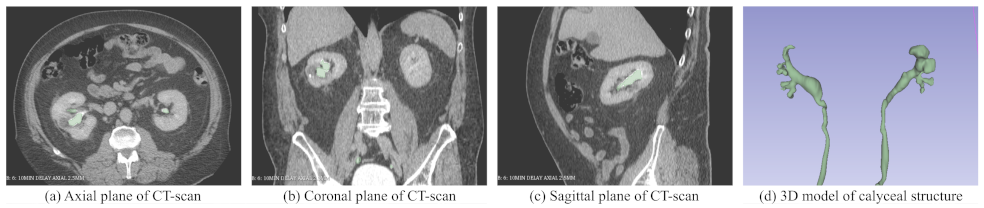

3. Generating 3D Model Patient CT Scans

3.1. Method

3.2. Haptic Feedback Based on 3D Models